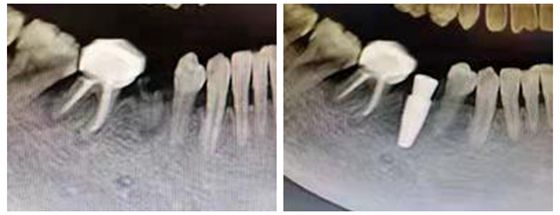

随着人们对牙齿的保护意识日益提升,医学技术的发达已经能够很好地解决牙缺失的难题,特别是数字化种植牙技术凭借着精准、快速、即种即用的优势成功帮助患者立长“新牙”。 术前CBCT显示牙根折断 湛女...